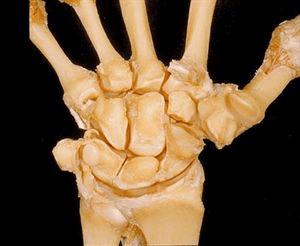

最详细解剖照片介绍和赏析

8.这张桡腕关节图以两排四个彼此相联的腕骨为特征,它显示了这些骨骼是如何与前臂和手指相连的。